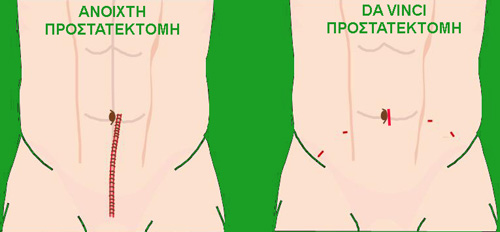

Είναι πια πραγματικότητα μεγάλες και πολύπλοκες χειρουργικές επεμβάσεις να εκτελούνται μέσω μικρών οπών (μικροσκοπικών τομών). Έτσι εξασφαλίζονται τα πλεονεκτήματα της οριστικής και πλήρους θεραπείας με την δυνατότητα για σημαντικά λιγότερο πόνο, συντομότερη παραμονή στο νοσοκομείο και γρηγορότερη επιστροφή στις καθημερινές δραστηριότητες καθώς και το σπουδαιότερο την δυνατότητα για καλύτερα κλινικά αποτελέσματα.

Κατά την ρομποτική προστατεκτομή 5 μικρές οπές μικρότερες του ενός εκατοστού πραγματοποιούνται στην κάτω κοιλιά μέσα από τις οποίες περνούν ειδικοί σωληνίσκοι (τα λεγόμενα τροκάρ) οι οποίες επιτρέπουν την ταχεία είσοδο και έξοδο των λαπαροσκοπικών και ρομποτικών εργαλείων στο εσωτερικό της κοιλιάς του ασθενή.

Όταν ο προστάτης και οι λεμφαδένες απελευθερωθούν από τους γύρω ιστούς τοποθετούνται αμέσως σε πλαστικό σάκο, ο οποίος αφαιρείται ανέπαφος στο τέλος της επέμβασης διαμέσου μίας από τις προϋπάρχουσες οπές, η οποία μεγεθύνεται ανάλογα για να περάσει και να εξέλθει ο σάκος που περιέχει τον προστάτη με τους λεμφαδένες. Έτσι ο προστάτης ούτε κομματιάζεται ούτε καρκινικά κύτταρα διασκορπίζονται. Μία λεπτή παροχέτευση τοποθετείται στην περιοχή της επέμβασης για να εκκενώνει τα υγρά της επέμβασης και εξέρχεται διαμέσου μίας από τις οπές των τροκάρ. Επίσης τοποθετείται ένας καθετήρας διαμέσου της ουρήθρας στην ουροδόχο κύστη λειτουργώντας σαν γέφυρα για την γρήγορη επούλωση της αναστόμωσης, της συρραφής ανάμεσα στην κύστη και στην ουρήθρα. Οι οπές των τροκάρ και η μικρή τομή, μέσα από την οποία πέρασε ο πλαστικός σάκος που περιείχε τον προστάτη, συρράπτονται χρησιμοποιώντας τεχνικές πλαστικής χειρουργικής για ελαχιστοποίηση των ουλών. Τα σημάδια της επέμβσης απορροφούνται ταχύτατα και ένα μήνα μετά φαίνονται μόνο ελάχιστα.

- Μικρές τομές και ελάχιστες ουλές

Η da Vinci Ριζική Προστατεκτομή για την θεραπεία του καρκίνου του προστάτη προσφέρει, σαν ελάχιστα επεμβατικό και τραυματικό χειρουργείο, πολυάριθμα πλεονεκτήματα συγκρινόμενη με την παραδοσιακή ανοιχτή επέμβαση. Χρησιμοποιώντας το σύστημα da Vinci, ο ρομποτικός ουρολόγος χειρουργεί μέσα από μικρές οπές των 5 με 12 χιλιοστών, οι οποίες έχουν το πάχος ενός μολυβιού.